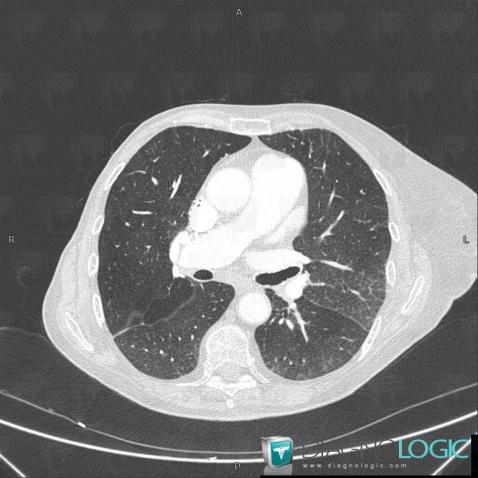

The images below illustrate this case for diagnoses Pulmonary edema, for the modalities (CT)

• Large symetric area of ground glass opacity

Pulmonary edema, Pulmonary parenchyma, CT

Here is the specific information in the key image above:

- Diagnosis Pulmonary edema, Location(s) Pulmonary parenchyma, with gamuts Large symetric area of ground glass opacity